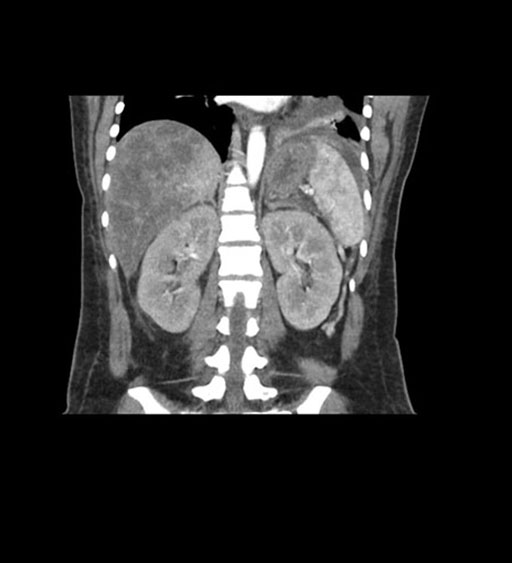

Imaging Analysis

Look through the patient's CT scan to identify any areas of concern for the necessary procedure.

Coronal Arterial

Coronal Venous